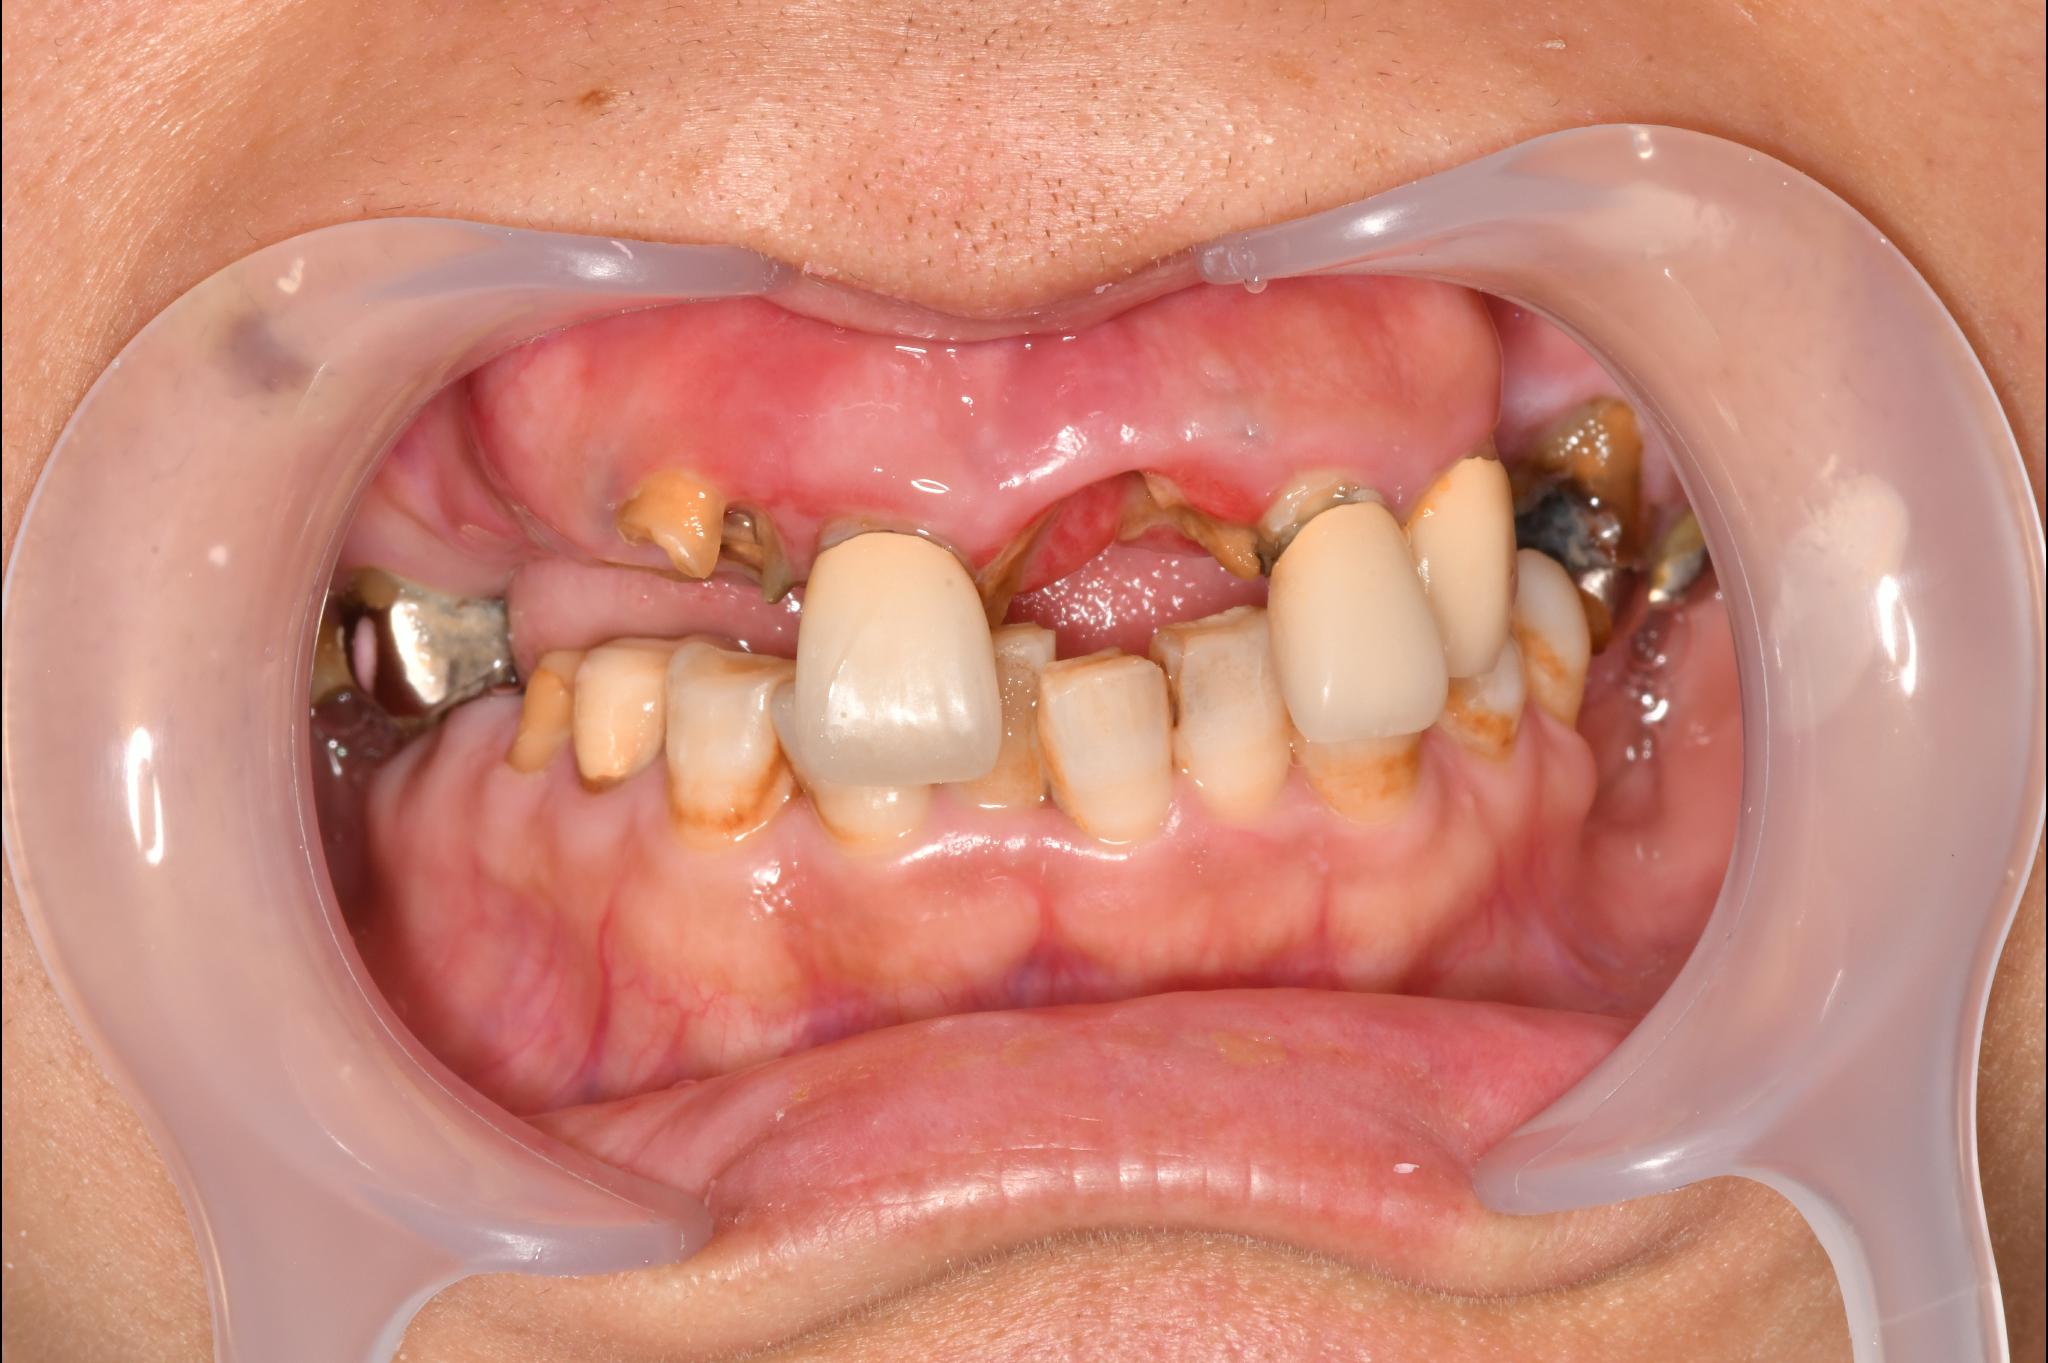

大分県 45歳(女性)

「マスクを外して人付き合いをしたい」

術前

内容 :上下顎オールオン4ザイゴマ0

費用 :4,365,900円

※モニター価格

期間 :半年

リスク:出血・腫れ・痺れ・痛み

「何度も通って恥ずかしい思いを長引かせたくない」という気持ちがありましたので、治療期間が短く、たった1日で固定式の歯が入ることがとても魅力的でした。

手術に対しては強い恐怖心を持っていましたが、実際には術中の記憶はほとんどなく、痛みを感じることもなく無事に終えることができました。

これまでは口元を気にして人との接触を避けていましたが、「笑顔で話したい」という明るい気持ちになれました。